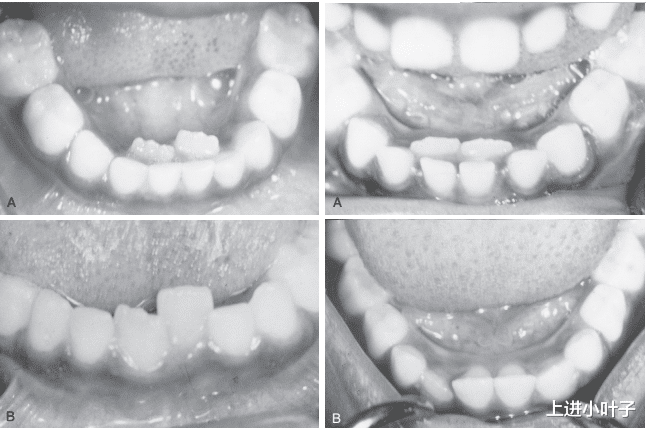

所谓“双排牙”,医学上称为乳牙滞留,指的是恒牙已经萌出,但对应的乳牙却迟迟没有脱落,导致新旧牙齿并存。很多家长误以为这是宝宝发育异常,其实大多和日常饮食密切相关。在过去,宝宝们常吃粗粮、硬食,咀嚼过程中会不断刺激乳牙牙根,促进其自然吸收脱落。但现在,为了方便宝宝吞咽、减轻消化负担,家长们会把食物做得过于精细:蔬菜剁成泥、肉类炖成羹、水果榨成汁,甚至米饭都煮得软烂如粥。

长期缺乏咀嚼锻炼,宝宝的颌骨发育会受到影响,乳牙牙根得不到足够的刺激,无法正常吸收萎缩,自然就“赖着不掉”。而恒牙又在正常时间萌出,只能从乳牙旁边“另寻出路”,形成难看又影响口腔健康的双排牙。更值得注意的是,双排牙不仅会导致牙齿排列不齐,还容易藏污纳垢,引发蛀牙、牙龈炎,甚至影响未来恒牙的正常发育。